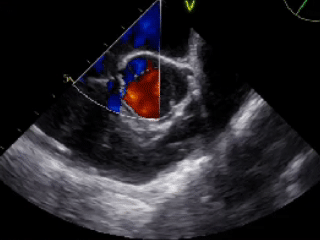

右心声学造影

静息状态:单帧图像气泡约20个(II级)

右房增压状态:第1个心动周期开始出现气泡,即刻充满左心(III级)